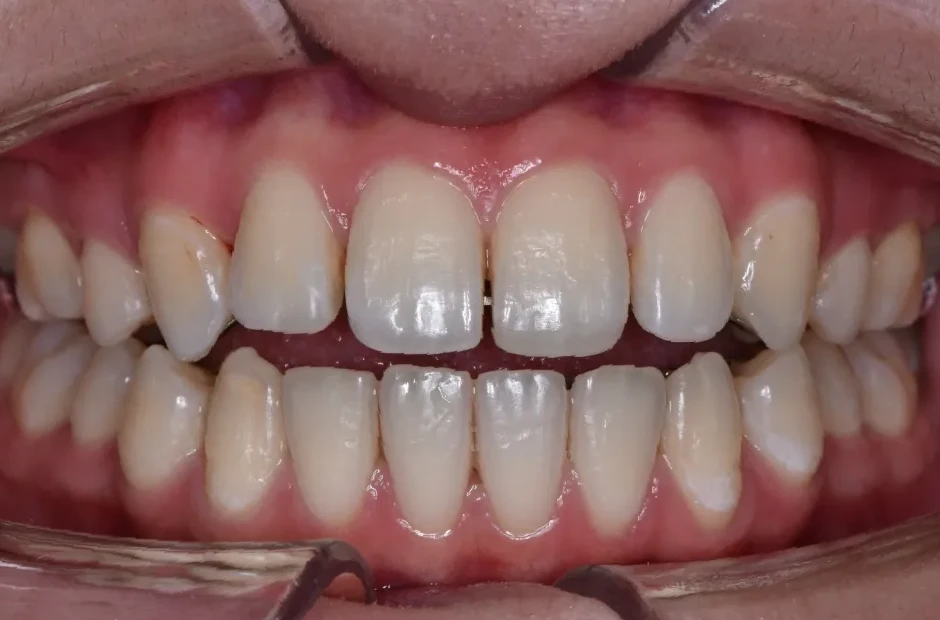

すきっ歯

| 診断名・主訴 | すきっ歯 |

|---|---|

| 年齢・性別 | 22歳・女性 |

| 治療期間・回数 | 2年半 30回 |

| 治療に用いた主な装置 | アンカー |

| 抜歯部位 | なし |

| 治療費 | 100万円(税抜) |

| リスク・副作用 | 装置による違和感・疼痛・歯肉退縮・歯根吸収・虫歯のリスクなど |

治療前

治療中

治療後